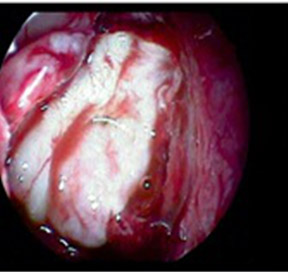

Fig 4: Underlay technique

Fig 5: Graft supported with surgicel

Prophylactic antibiotics were given to prevent meningitis. Intravenous mannitol twice daily and tablet acetazolamide 250mg three times daily (8th hourly) was given to control intracranial pressure. As there was no response for medical treatment, surgical repair was planned. The surgery was done under general anaesthesia. The nasal cavity was packed with 4% xylocaine and 1:200000 adrenaline. After infiltration, antero-inferior part of middle turbinate was harvested as pedicle graft. Site of leak identified with endoscope, mucosalflap of middle turbinate placed over the defect by underlay technique (Fig. 4). Harvested middle turbinate with pedicle is rotated to snugly fit in between the well placed mucosal flap, skull base and the remnant middle turbinate. The repaired area was supported with surgicel. The nasal packing was done with antibiotic soaked ribbon gauze. Nasal pack was removed after 48 hrs. Follow up after one month showed no evidence of recurrence.